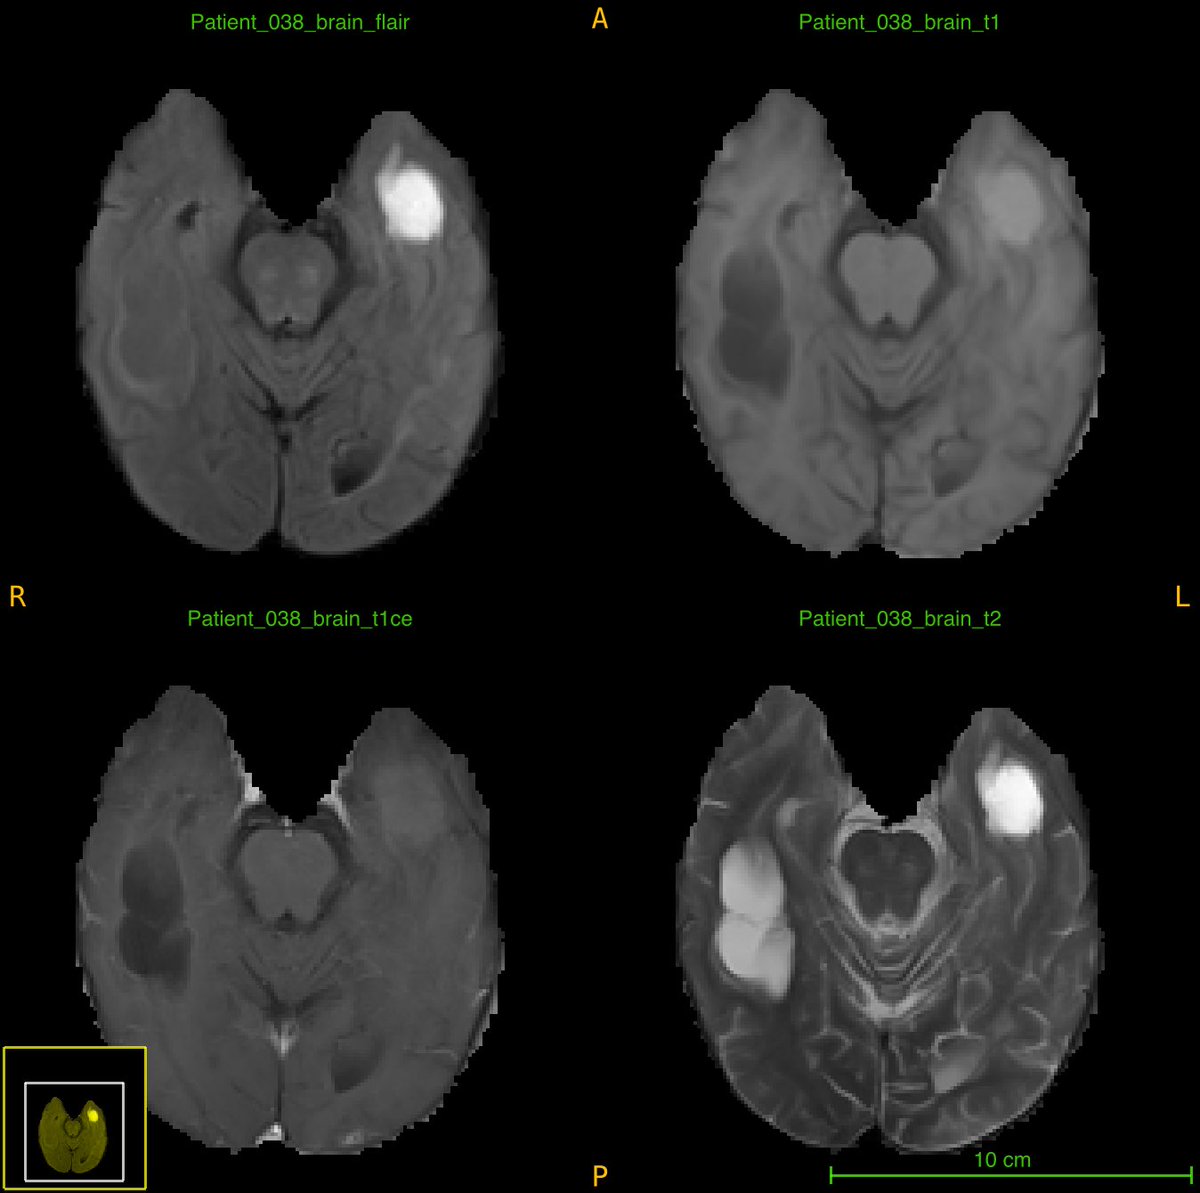

"Discover your passion & embrace it without overthinking" - one of the many inspiring lessons we learned today from @rad_Umber. #BraTS annotator team explored imaging informatics, focusing on improved patient care through better data management. Call us (junior) II experts! 🌟